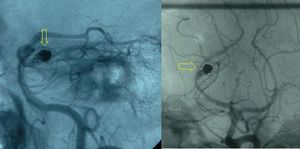

يتم الوصول للعضو المطلوب عن طريق سلوك التوجيه أو القساطر. وعلى حسب العضو، قد يكون الوصول له صعبًا للغاية ومستهلكًا للوقت. يتم تحديد وضع الشريان أو الوريد السليم الذي يغذي النسيج المرضي عن طريق تصوير الأوعية بالطرح الرقمي. يتم استخدام تلك الصور بعد ذلك كخريطة لطبيب الأشعة التدخلية للوصول إلى الوعاء الدموي الصحيح عن طريق استخدام قسطرة أو سلك مناسبـ بالاعتماد على 'الشكل' التشريحي المحيط.

بمجرد إدخال السدادة الصناعية بنجاح، يتم تصوير الأوعية بالطرح الرقمي مرة أخرى للتأكد من نجاح العملية.